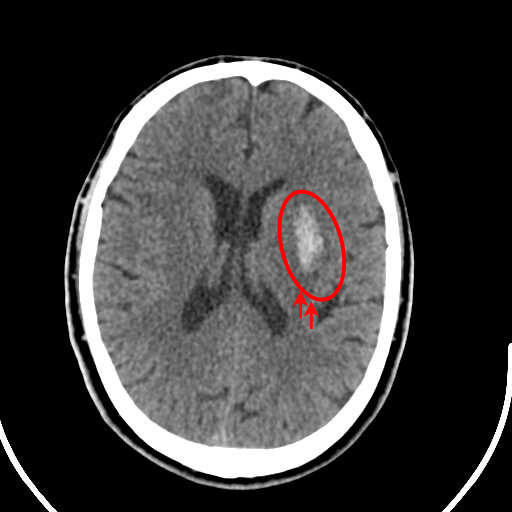

(b) Brain CT scan showing CSDH

Figure 3: (a) Brain CT scan showing ASDH, characterized by recent bleeding with high-density regions, (b) Brain CT scan showing CSDH, indicating older, low-density blood accumulation.